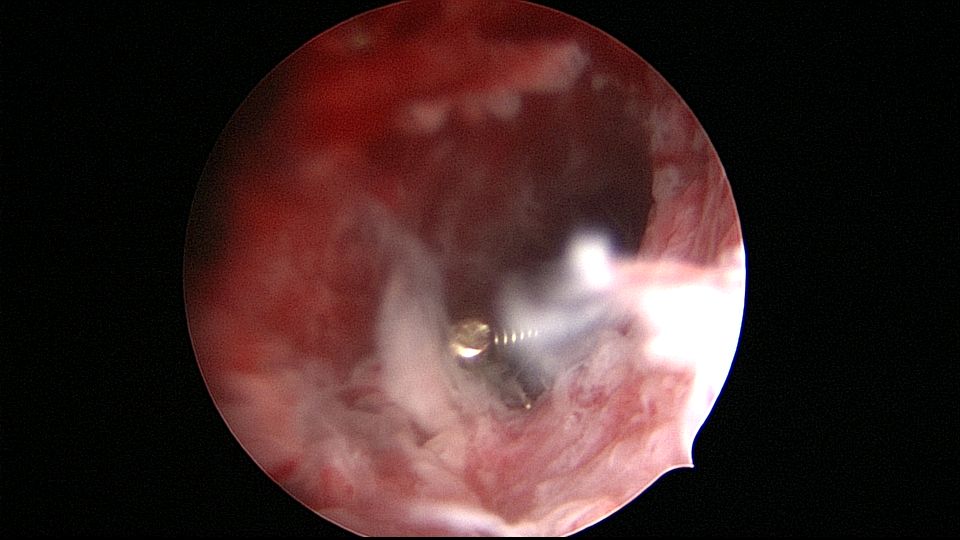

患者45岁,G1P2,剖宫产双胎1次(自然妊娠)。安环23年,异常子宫出血月经淋漓不尽2个月,外院取环残留,环断裂,外院医生述取出约10cm变形环段,腹部平片见O型环断裂,断端指向宫颈管。宫颈位于前穹隆顶端,暴露困难,艰难置入宫腔镜,见内膜杂乱,反复寻找才发现O型环残环,残环两侧与宫壁嵌顿,异物钳抓取数次均滑脱,顺宫颈管向下寻找,在宫颈管中上段找到环断端,异物钳缓慢拉出断端至宫颈外口,中弯钳配合卵圆钳牵拉,环断裂,取出约10cm环残段。宫腔镜再次进入宫腔,找到剩余残环,异物钳夹取,多次滑脱,取环钩顺着镜鞘外侧进入宫腔,钩住残环,缓慢下拉至宫颈外口,中弯钳配合卵圆钳拉出约12cm环残段,宫腔镜再次探查宫腔,镜下未见环残留,取内膜送病检。术后病人离院时复查B超,有强回声带,因宫腔少许气体干扰,无法确定是否环残留,嘱病人一周后复查B超,确定无环残留。第一次遇到这么脆弱的金属圆环,很容易断裂。病检为子宫内膜增生,不伴非典型增生。